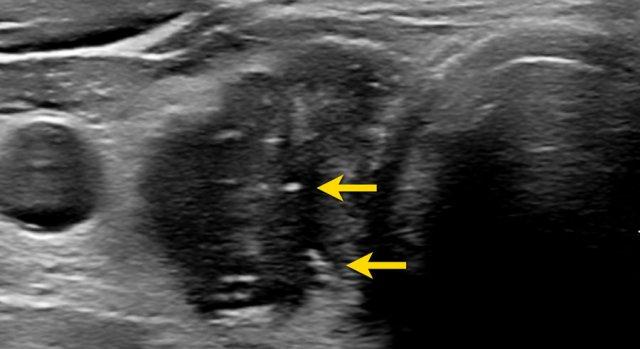

Tổn Thương Giảm Âm Rõ Rệt

Tổn thương giảm âm rõ rệt có độ hồi âm thấp hơn so với mô cơ bình thường.

Lưu ý rằng, trong hình ảnh được cung cấp, tổn thương có độ giảm âm cao hơn so với các cơ dải (được chỉ bởi các mũi tên).